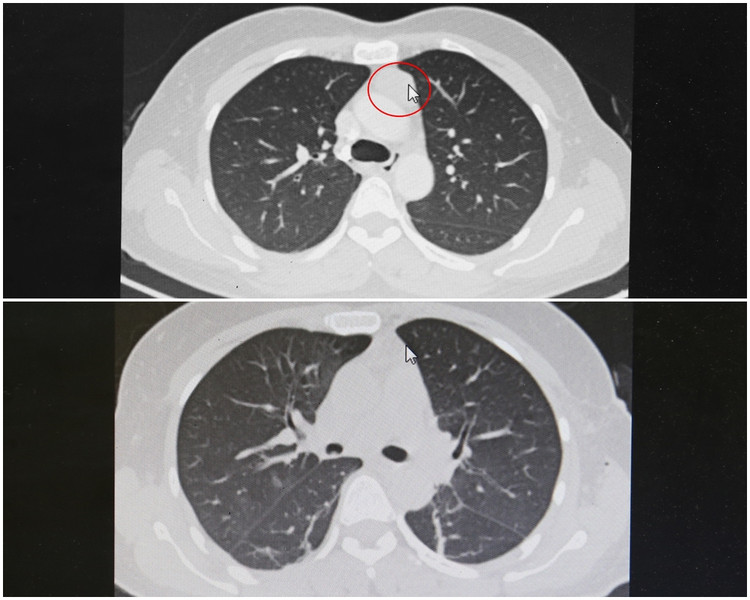

Kết quả chụp cắt lớp vi tính lồng ngực phát hiện khối u tuyến ức, kích thước khoảng 18x30cm. Các bác sĩ chẩn đoán bệnh nhân bị u tuyến ức và chỉ định phẫu thuật nội soi lồng ngực cắt toàn bộ tuyến ức.

| Hình ảnh chụp cắt lớp lồng ngực khối u tuyến ức trước và sau phẫu thuật lấy u |